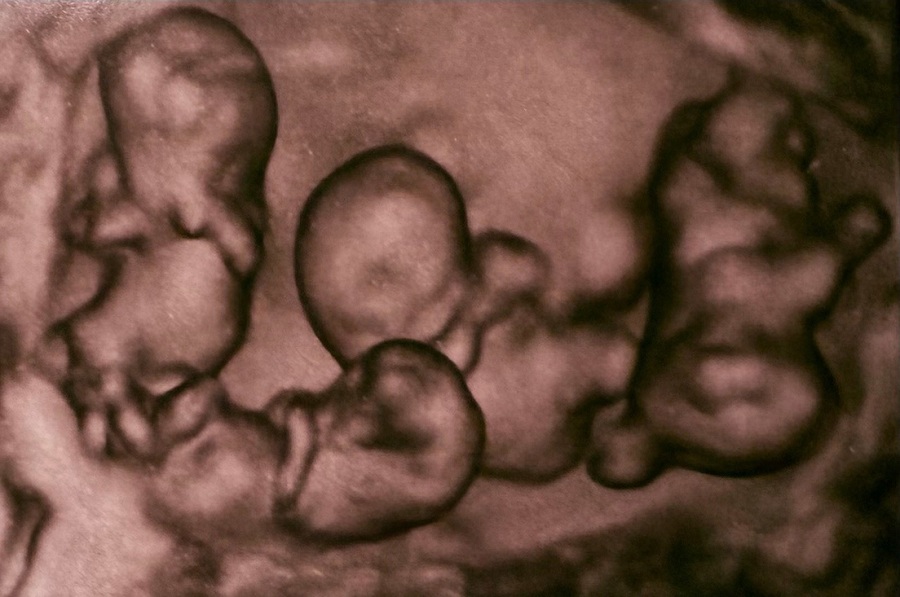

Salud.- El pasado 2 de abril nacieron en San Petersburgo unas cuatrillizas monocigóticas, es decir, cuatro bebés idénticas provenientes de un solo óvulo fecundado, un hecho sin precedentes en la historia de la medicina de Rusia, recogen este domingo medios locales.

El acontecimiento tuvo lugar en el hospital de maternidad Nº.17, de la ciudad rusa. Las cuatro bebés nacieron a las 32 semanas de gestación. De acuerdo con especialistas, este tipo de embarazo es extremadamente raro, ya que se estima que ocurre una vez cada 15,5 millones de partos.

Un equipo de obstetras, anestesiólogos y neonatólogos encabezados por el director del hospital realizó la compleja intervención, garantizando la seguridad de la madre y las recién nacidas. De acuerdo con la institución médica, las niñas presentaron condiciones de salud acordes a su edad gestacional, con pesos que oscilaron entre 1,36 y 1,64 kilogramos.